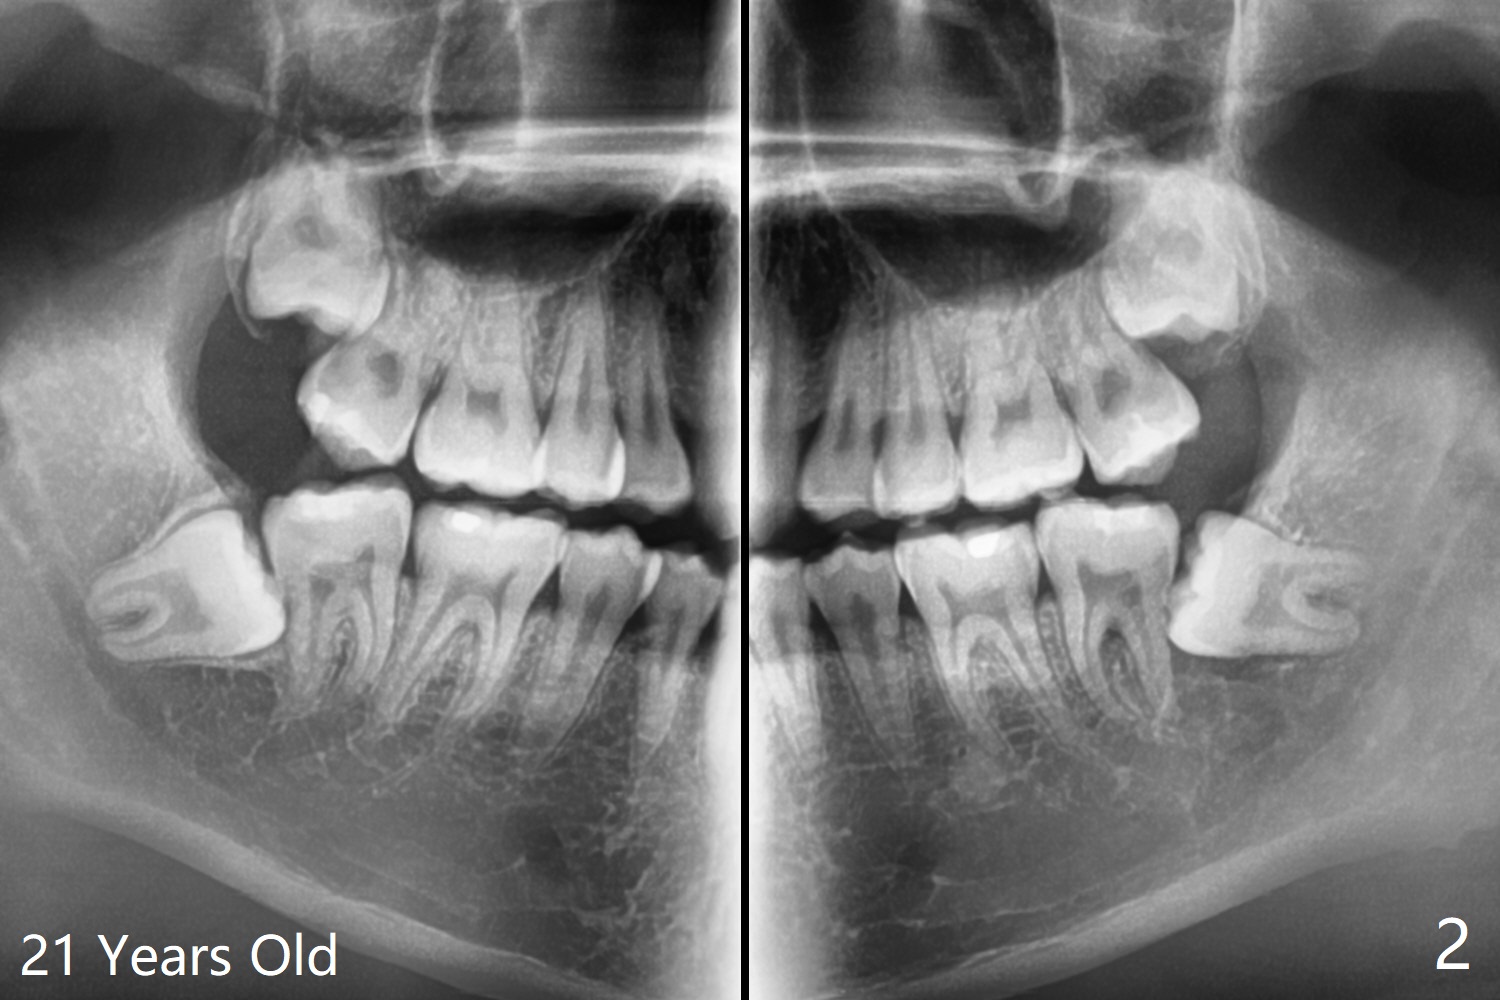

A 21-year-old man returns to clinic with pain and swelling at #17 (Fig.1,2). After multiple sectioning, the tooth is extracted with insertion of collagen plug post extraction in the late afternoon. The patient complains of sharp pain during local anesthetic injection. Postop paresthesia is gradually getting better, but gets worse 2 months postop (Fig.3,4). Neurotin is prescribed. Vitamin B1 and B12 are recommended. OMFS is suggested. 21岁男因左下智齿肿痛要求拔除(图一,二),术中发现轻度颊侧阻生,使用一只利多卡因,一只Septocaine,一般前者block anesthesia,后者infiltration。多次用手机切割牙齿,拔除后牙槽窝放置一个胶原塞(减少术后干槽症),4-0铬羊肠线缝合。术后两个月病人突然回来,主诉局麻注射造成剧痛,术后下嘴唇麻木开始逐渐好转,最近麻木突然加重(图三,四)。左下智齿牙槽窝已经愈合。处方:Neurotin;推荐维生素B1, B12;建议口外会诊。还能做什么?